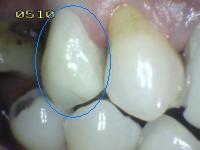

1 |

Sellador parcial |